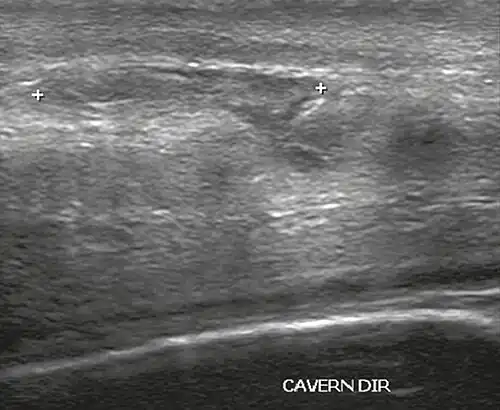

In the ultrasound examination, a lesion of the tunica albuginea presents as an interruption in (loss of continuity of) the echoic line representing it (Figure 4). Small, moderate, or broad hematomas demonstrate the extent of that discontinuity. Intracavernous hematomas, sometimes without the presence of a tunica albuginea fracture, can be observed when there is a lesion of the smooth muscle of the trabeculae surrounding the sinusoid spaces or the subtunical venular plexus.[2]

Figure 4 A: Ultrasound of the penis, right lateral view. Longitudinal section showing rupture of the tunica albuginea with an adjacent 1.92 cm hematoma (between calipers), due to trauma.[2] -

B: Axial T2-weighted turbo spin-echo magnetic resonance imaging scan showing left-sided discontinuity of the tunica albuginea (arrow), secondary to fracture.[2]